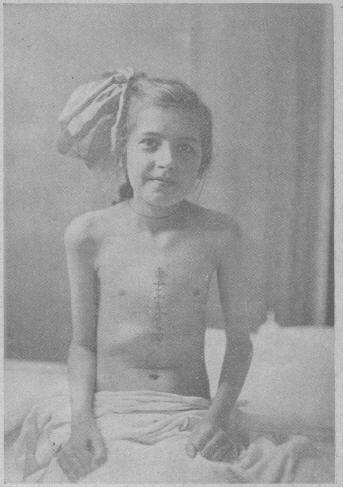

1948年6月3日

Sidney Farber报道了治疗儿童早期白血病的发现。根据传统认识,如果白血病儿童给予叶酸的话,他们的急性白血病会恶化,根据这个理论,Farber给予儿童一个叶酸抑制剂,就是氨嘌呤,16名儿童中的10个获得了明显的疗效。尽管还存在很多问题,例如副作用和只是临时缓解,但这毕竟是一个开始。